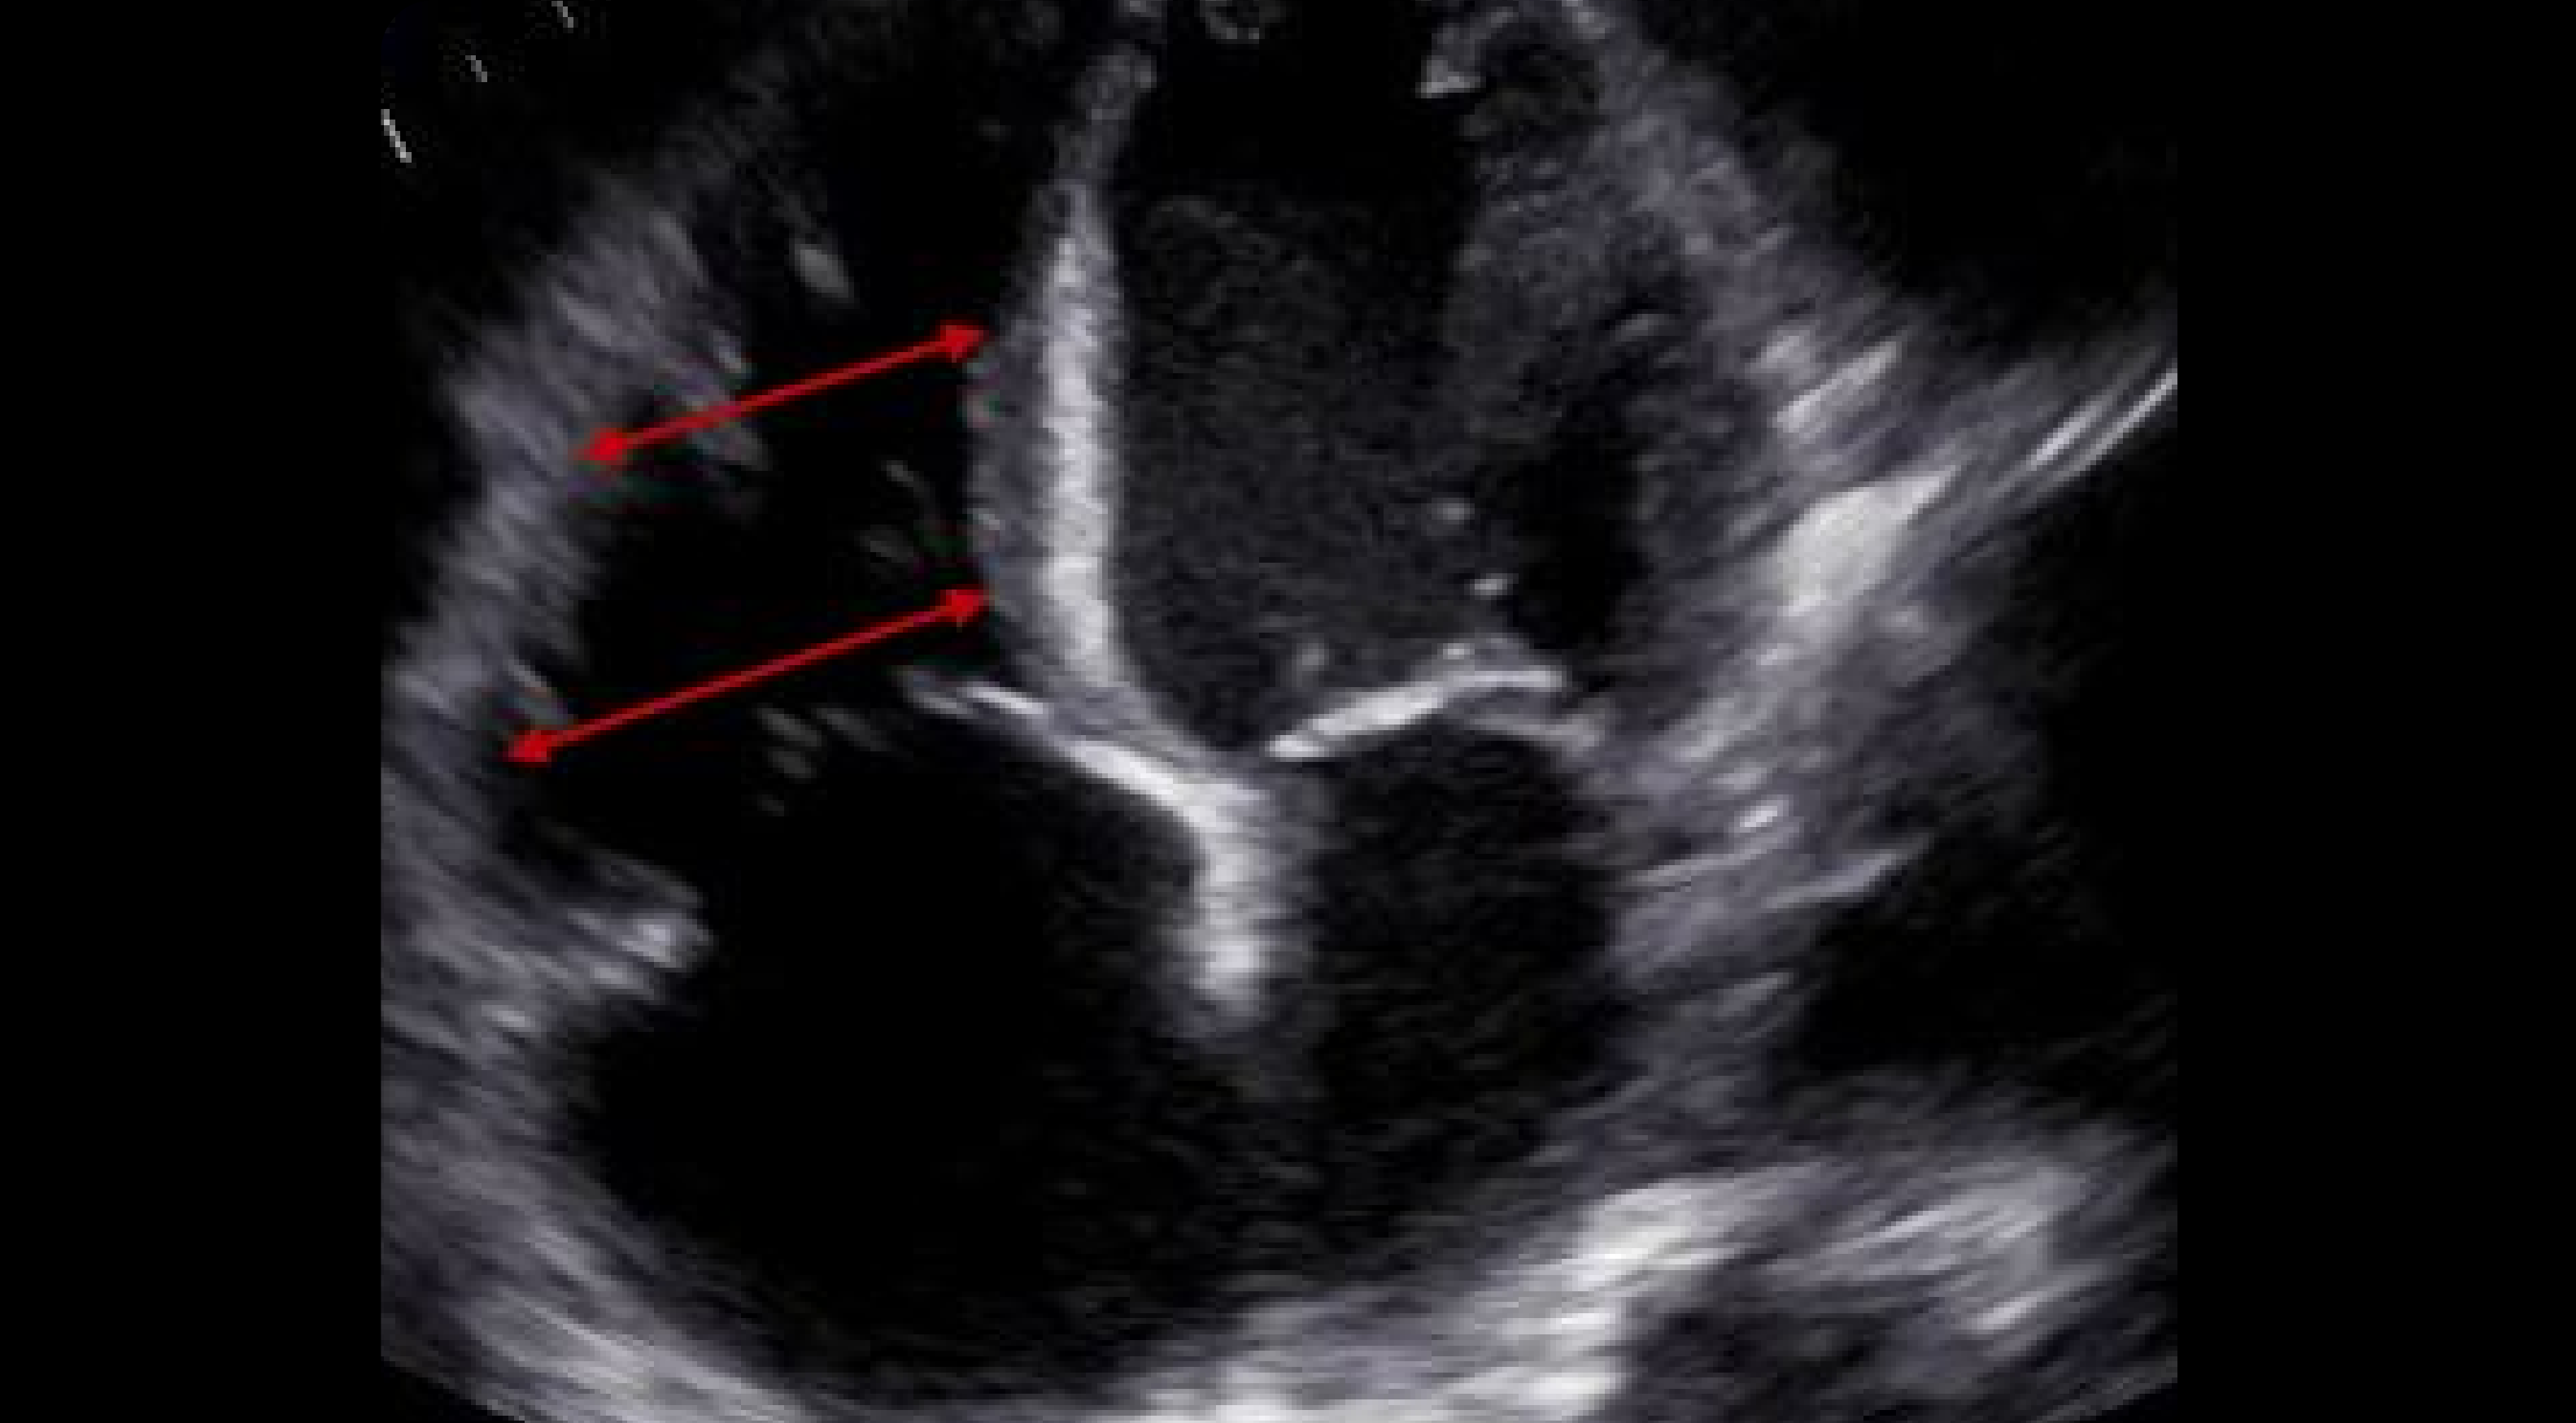

Right Ventricular Size And Measurements On Pocus Echo vrogue.co Right Ventricle Diameter Echo the parameters to be performed and reported should include a measure of right ventricular (rv) size, right atrial (ra) size, rv systolic function (at least. Systolic and diastolic function, and rv systolic. the american society of echocardiography recommendations for cardiac chamber. the complex anatomy of the right ventricle requires special considerations and echocardiographic. Right Ventricle Diameter Echo.

2D echo showing normal size of the right ventricle Download Right Ventricle Diameter Echo the american society of echocardiography recommendations for cardiac chamber. Systolic and diastolic function, and rv systolic. the complex anatomy of the right ventricle requires special considerations and echocardiographic. the parameters to be performed and reported should include a measure of right ventricular (rv) size, right atrial (ra) size, rv systolic function (at least. Right Ventricle Diameter Echo.

What is the normal RV size ? How to measure it by echocardiography Right Ventricle Diameter Echo Systolic and diastolic function, and rv systolic. the parameters to be performed and reported should include a measure of right ventricular (rv) size, right atrial (ra) size, rv systolic function (at least. the complex anatomy of the right ventricle requires special considerations and echocardiographic. the american society of echocardiography recommendations for cardiac chamber. Right Ventricle Diameter Echo.